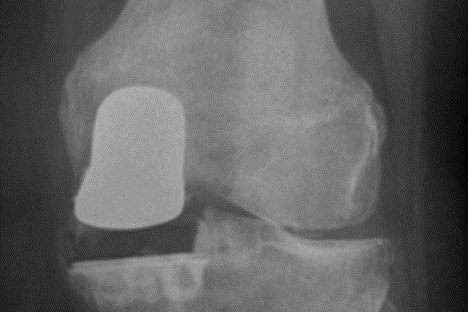

Er pasientene over 70 år vil bare 5 % av protesene være skiftet ut etter 10 år (Furnes - Failure Mechanisms 2007.pdf). Du vil således ha en stor sjanse for å beholde protesen resten av livet dersom du er over 70 år. Ved en-kammerartrose kan kirurgen velge en-kammerprotese (unikondylær protese). Dette er en noe mer krevende protese å operere for kirurgen, men den gir vanligvis noe bedre bevegelse og funksjon enn totalprotese. Bakdelen er 2 ganger økt risiko for reoperasjon pga løsning og brudd rundt protesen (Furnes - Failure Mechanisms 2007.pdf, Art_Dyrhovden-Have the causes of.pdf). (Figur 4: Røntgenbilde av unikondylær kneprotese.)